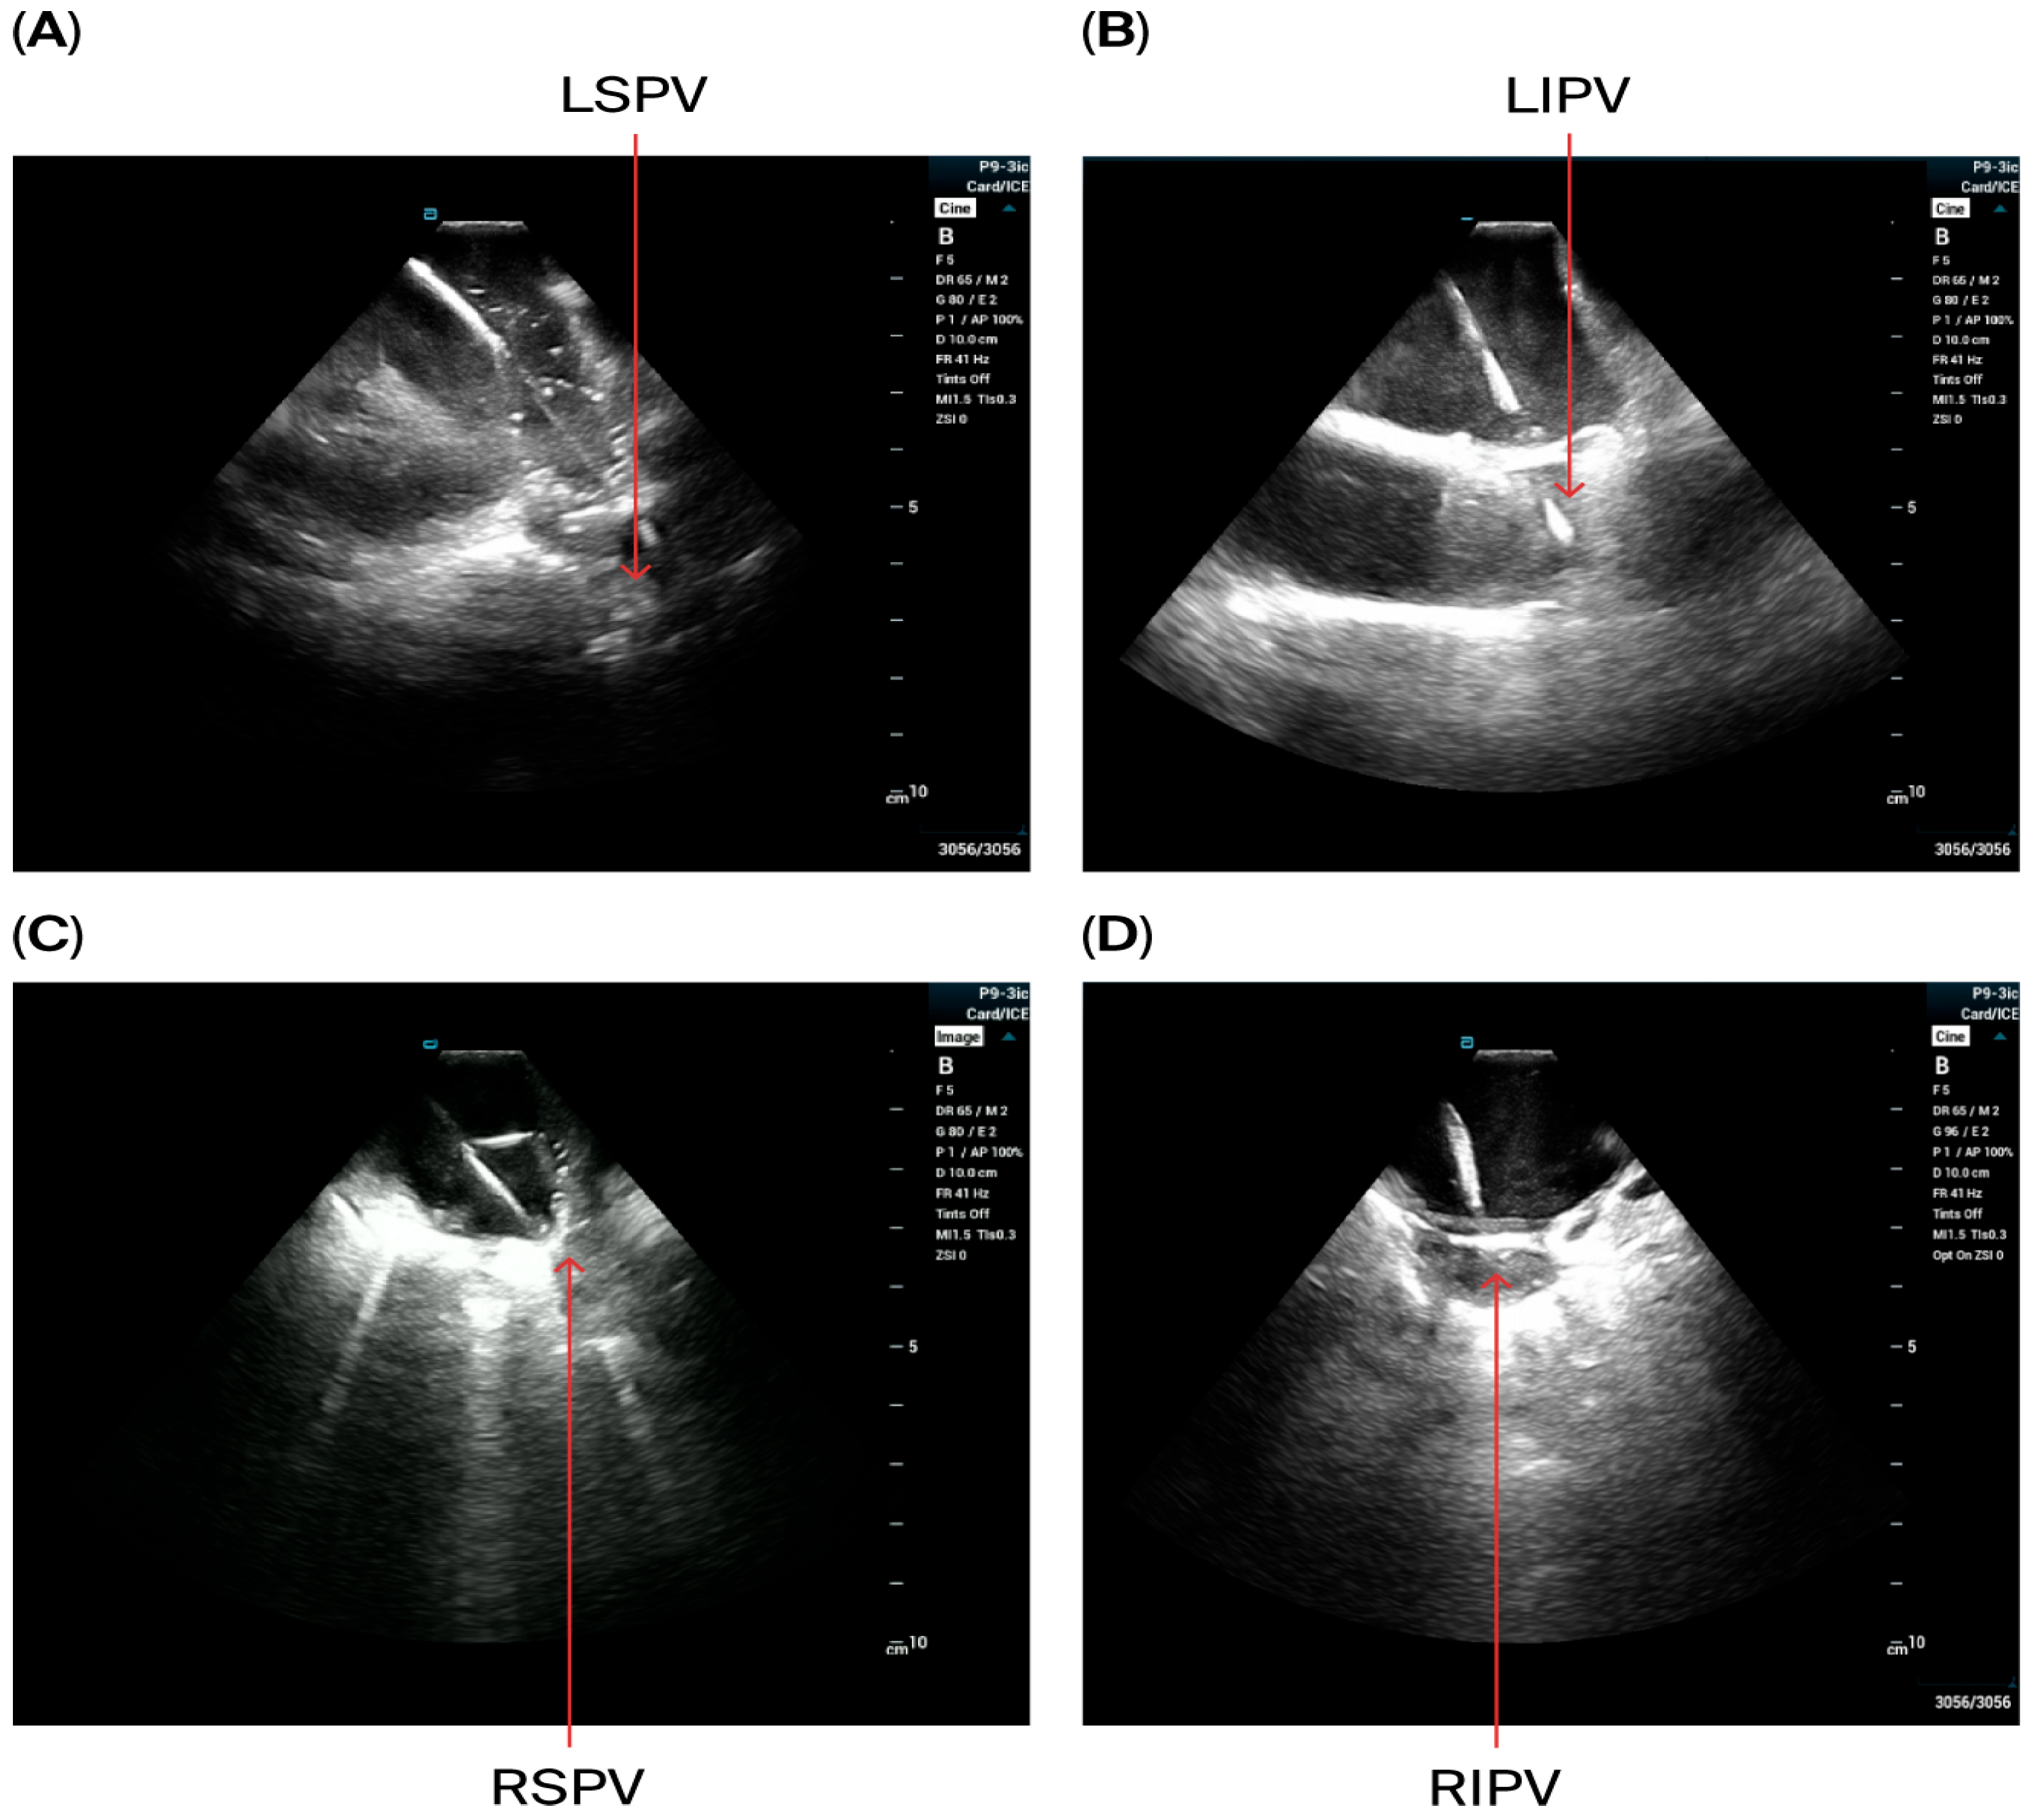

- A circular mapping catheter (CMC) or high-density catheter (with repeated ablation) was advanced to the LA via the Faradrive sheath. Electroanatomic mapping of the LA, including detailed voltage assessment was performed. Then, over the J-tip wire, the Farawave pentaspline catheter was advanced to the LA via the Faradrive sheath. The 0.035-inch J-tip guidewire was attached to the EnSite mapping system’s pin box via a DuoMode extension cable (Boston Scientific, Marlborough, MA, USA) for additional visualization in LA and pulmonary veins. ICE catheter imaging was used to ensure appropriate catheter positioning and catheter–tissue contact with each PV and LAPW PFA lesion delivered. Prior to ablation, 0.2 mg of intravenous glycopyrrolate was administered to all patients to avoid vagal reactions during PVI.

- PV isolation was performed with the PFA catheter placed at the PV ostium, with 4 applications in the basket configuration and 4 in the flower configuration for a total of 8 applications per PV. Appropriate rotation of the catheter following 2 applications in each position was assured with LA ICE and EAM visualization. Two additional applications in the flower configuration were delivered at the operator’s discretion in the left and right carina, towards the LA ridge and septal aspect of the right pulmonary veins based on the anatomy and presence of atrial potentials.

- LAPW isolation was achieved with overlapping lesions placed in the flower configuration, with 2 application per site. With the J-tip wire in the left PV serving as a ‘hook’, rotating the catheter clockwise in the flower configuration allowed ablation of the posterior wall near the left veins; similarly, with the J-tip wire in the right pulmonary veins, rotating the catheter counterclockwise allowed appropriate contact for the posterior wall isolation near right veins. Remaining mid-posterior wall was ablated with overlying lesions in the flower configuration. ICE was used with each ablation application to ensure optimal contact.

- For superior vena cava (SVC) isolation, the ICE catheter was retracted to the top right of the atrium to guide the ablation procedure. Prior to and after ablating the SVC, the CMC was placed at the junction of the SVC and right atrium to map the phrenic nerve and to detect potential phrenic nerve injury. Then, the Pentaspline catheter was placed at the junction of right atrium and SVC (the lower edge of the right pulmonary artery level in ICE imaging). A total of 4 applications in the basket configuration were delivered (2 followed by 2 other applications after rotating the catheter 30 degree), and heart rate was monitored during the procedure.